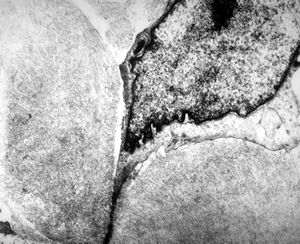

F,79y. | jejunum - amyloidosis